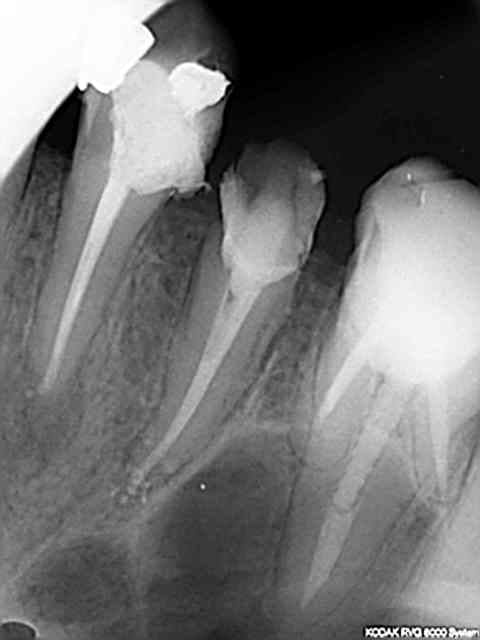

chicot29

1 .Essayage cones en place, couper ce qui dépasse le cas échéant ( une sur instrumentation ca arrive)

2. scellement des cones.

3. couper les cones au friendo puis phase de descente au friendo ( qui est un heater plugger je le rappelle) et compactage au machtou.

4. coincer les chutes de gutta à l' entrée des canaux et les thermo-compacter au mac spadden.

C'est pret ! -))))